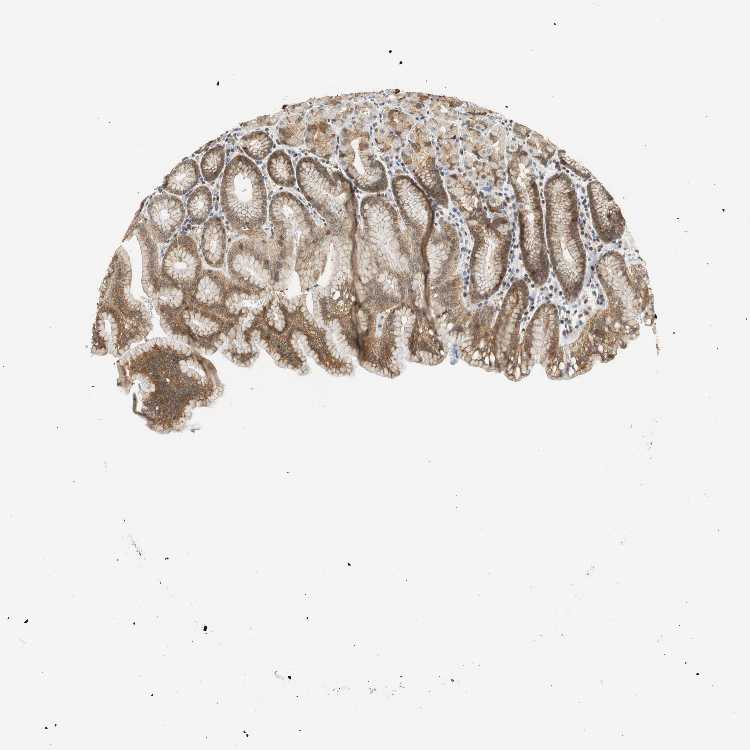

STOMACH 2 - Antibody stainingi

Antibody staining in the annotated cell types in the current human tissue is reported as not detected, low, medium, or high, based on conventional immunohistochemistry profiling in selected tissues. This score is based on the combination of the staining intensity and fraction of stained cells.

Each image is clickable and will lead to virtual microscopy that enables deeper exploration of all samples and also displays staining intensity scores, fraction scores and subcellular localization as well as patient and tissue information for each sample.

Antibody HPA044487Antibody CAB004656

Glandular cells MediumMedium